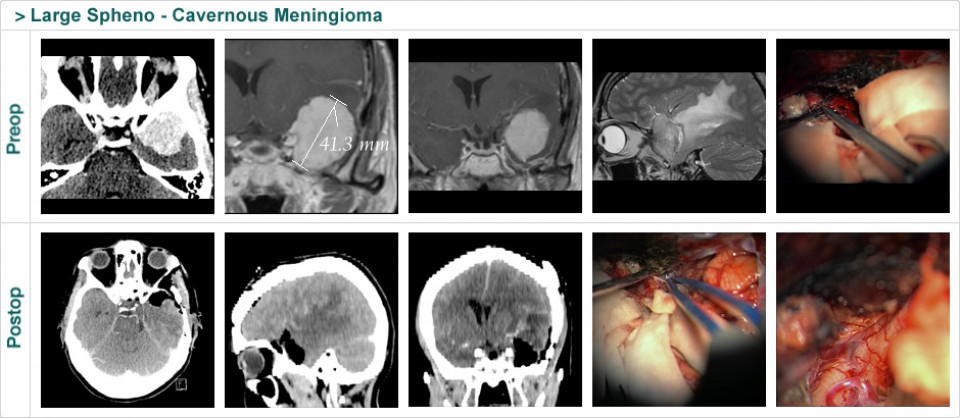

Dr. Attia is an attending neurosurgeon and the director of skull base surgery service in the department of neurosurgery at Sheba Medical Center in Tel HaShomer. His specialty focuses on skull base and cerebrovascular neurosurgery.